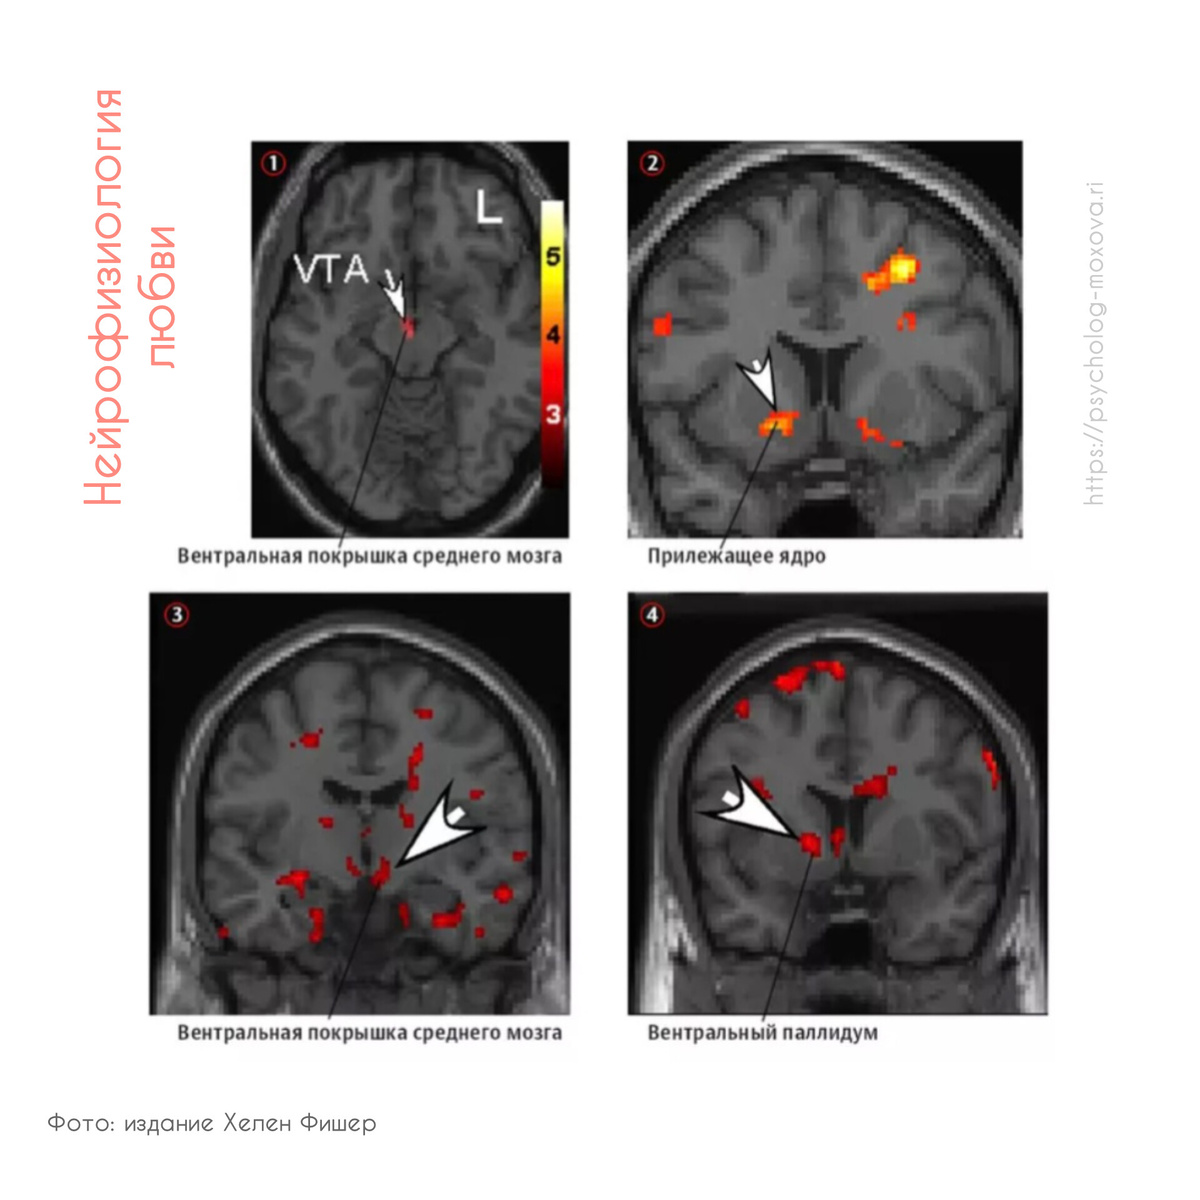

На МРТ головного мозга добровольцев удалось запечатлеть нейроны определенных отделов, которые руководят любовью, а именно, дофаминовая система. Она включает в себя: вентральнау покрышку среднего мозга (ВТА- вентральная тегментальная область), хвостатое ядро (Caudate Nucleus), полосатое тело или стриатум (striatum), медиальную префонтальную кору.

Кстати, по результатам исследований Хелен Фишер у супружеских пар, которые счастливо живут больше 20 лет, активна не только "вентральная покрышка среднего мозга, связанная с романтическим чувством и чувством глубокой привязанности", но и "вентральный паллидум, отвечающий за счастье".